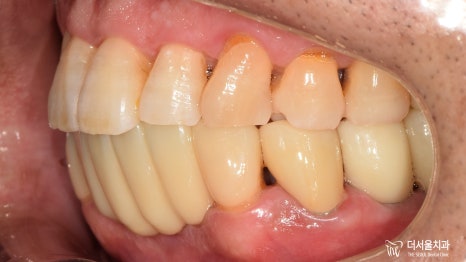

임플란트 치과 의 좌측 과정은

최종 보철을 올려드리며 모두 마무리가 되었습니다.

환자께서는 우측 어금니 또한 상실되어 있었는데요.

현재, 우측 식립을 기다리고 있는 중입니다.